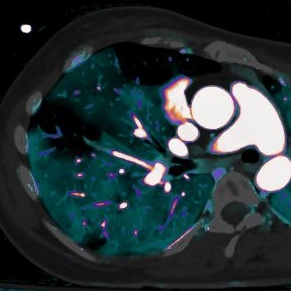

....notice how well the perfusion defect on iodine overlay stands out in the corresponding vascular territory